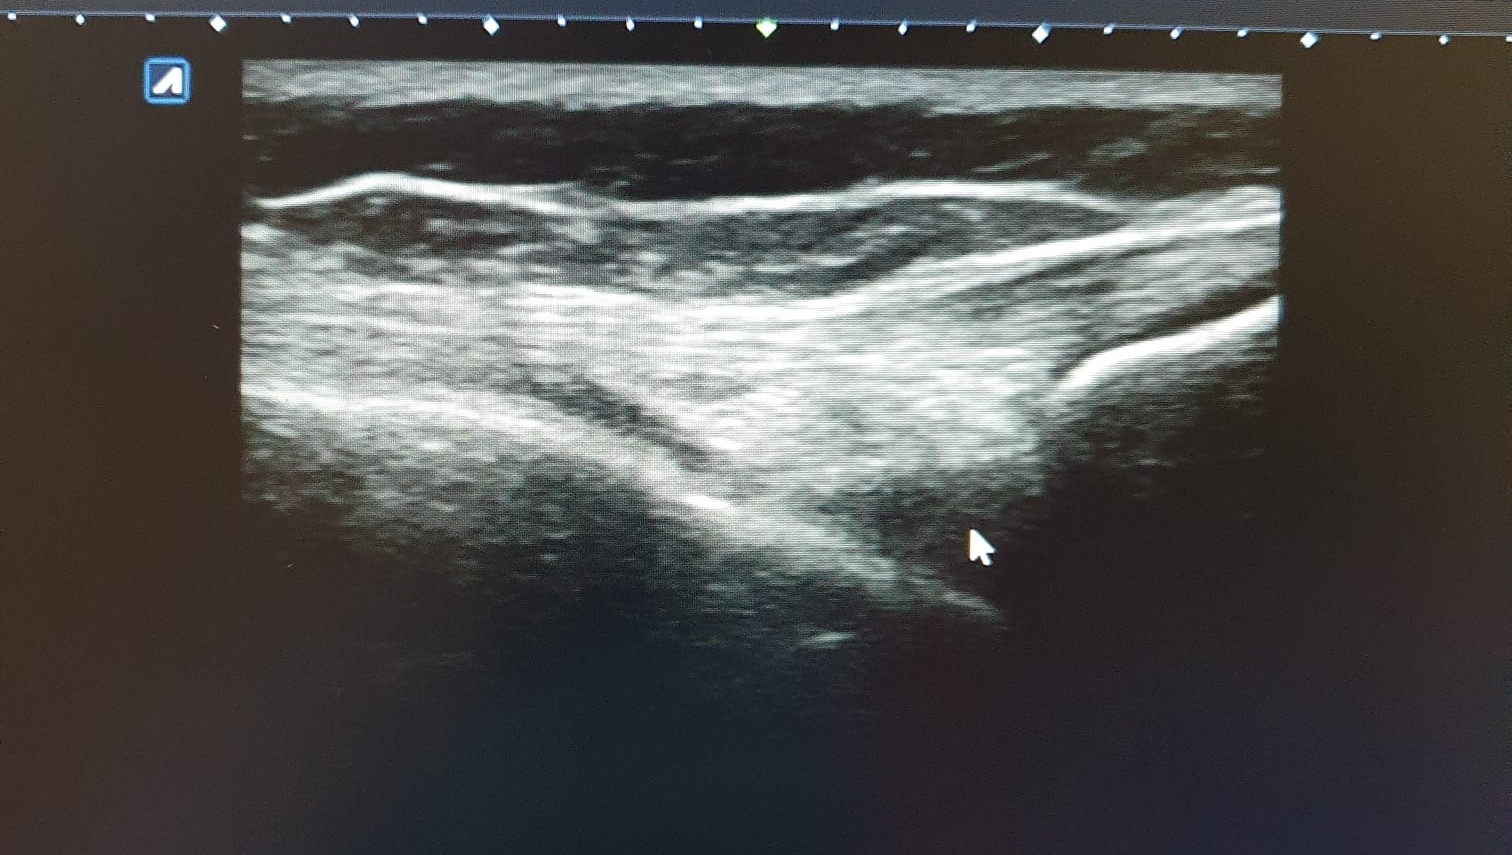

Hallazgos ecográficos

Ecografía de rodilla. Compartimento lateral: imagen anecoica/hipoecoica 10 x 5 mm en zona proximal de ligamento colateral lateral, sugestivo de rotura parcial. Compartimento posterior: imagen anecoica 20 x 30 mm sugestivo de quiste de Baker. No otras alteraciones ecográficas.